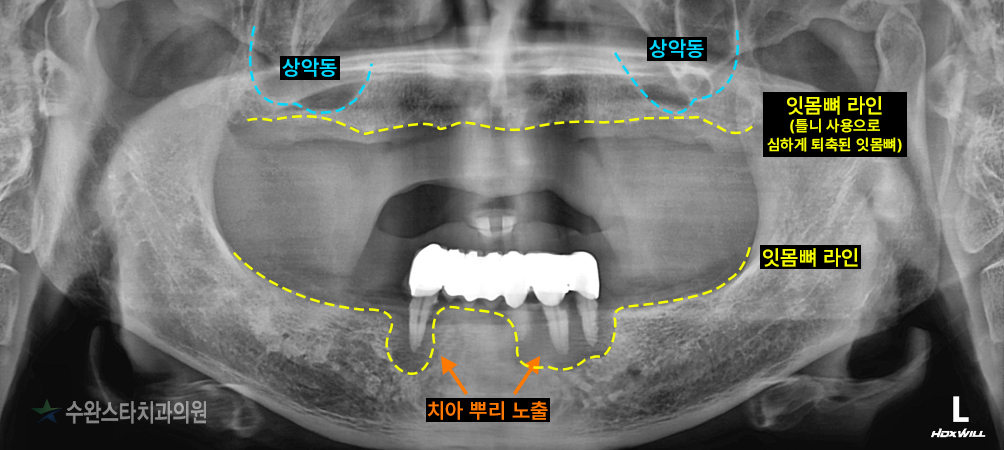

내원 시 파노라마 사진입니다.

하악 잔존 치아의 잇몸뼈가 녹아

치아 뿌리가 노출된 모습 보이시나요?

상악도

상악동 라인과 잇몸뼈 라인이

거의 맞닿아 있는 것으로 보아

임플란트를 식립하기에

잇몸뼈가 부족합니다.

상악, 하악 모두 뼈가 부족해

임플란트를 식립하려면

뼈 이식이 필요한 상태였습니다.